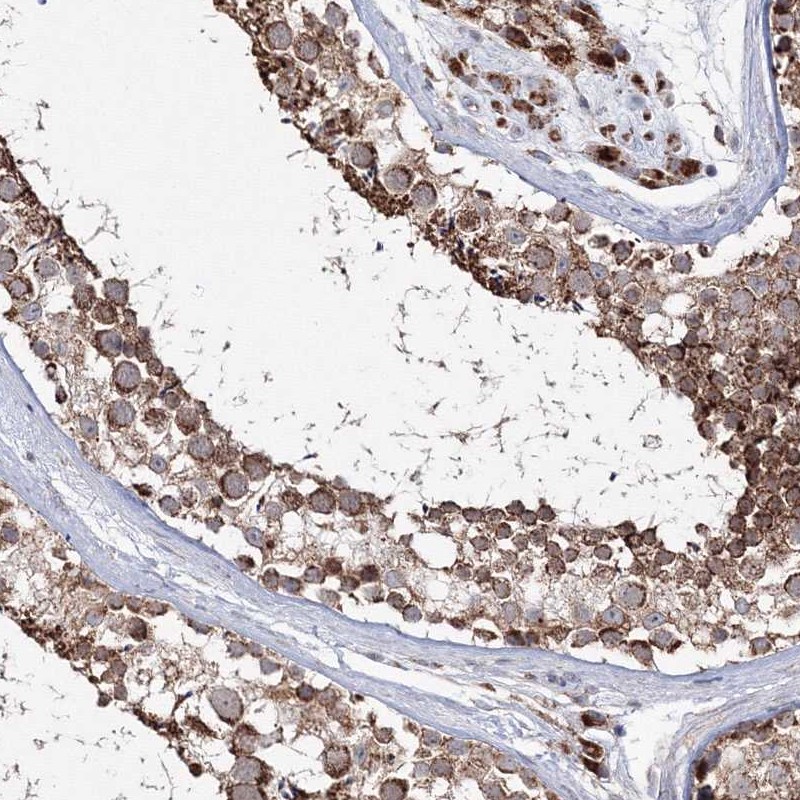

Immunohistochemistry analysis in human testis and pancreas tissues using Anti-PEX13 antibody. Corresponding PEX13 RNA-seq data are presented for the same tissues.